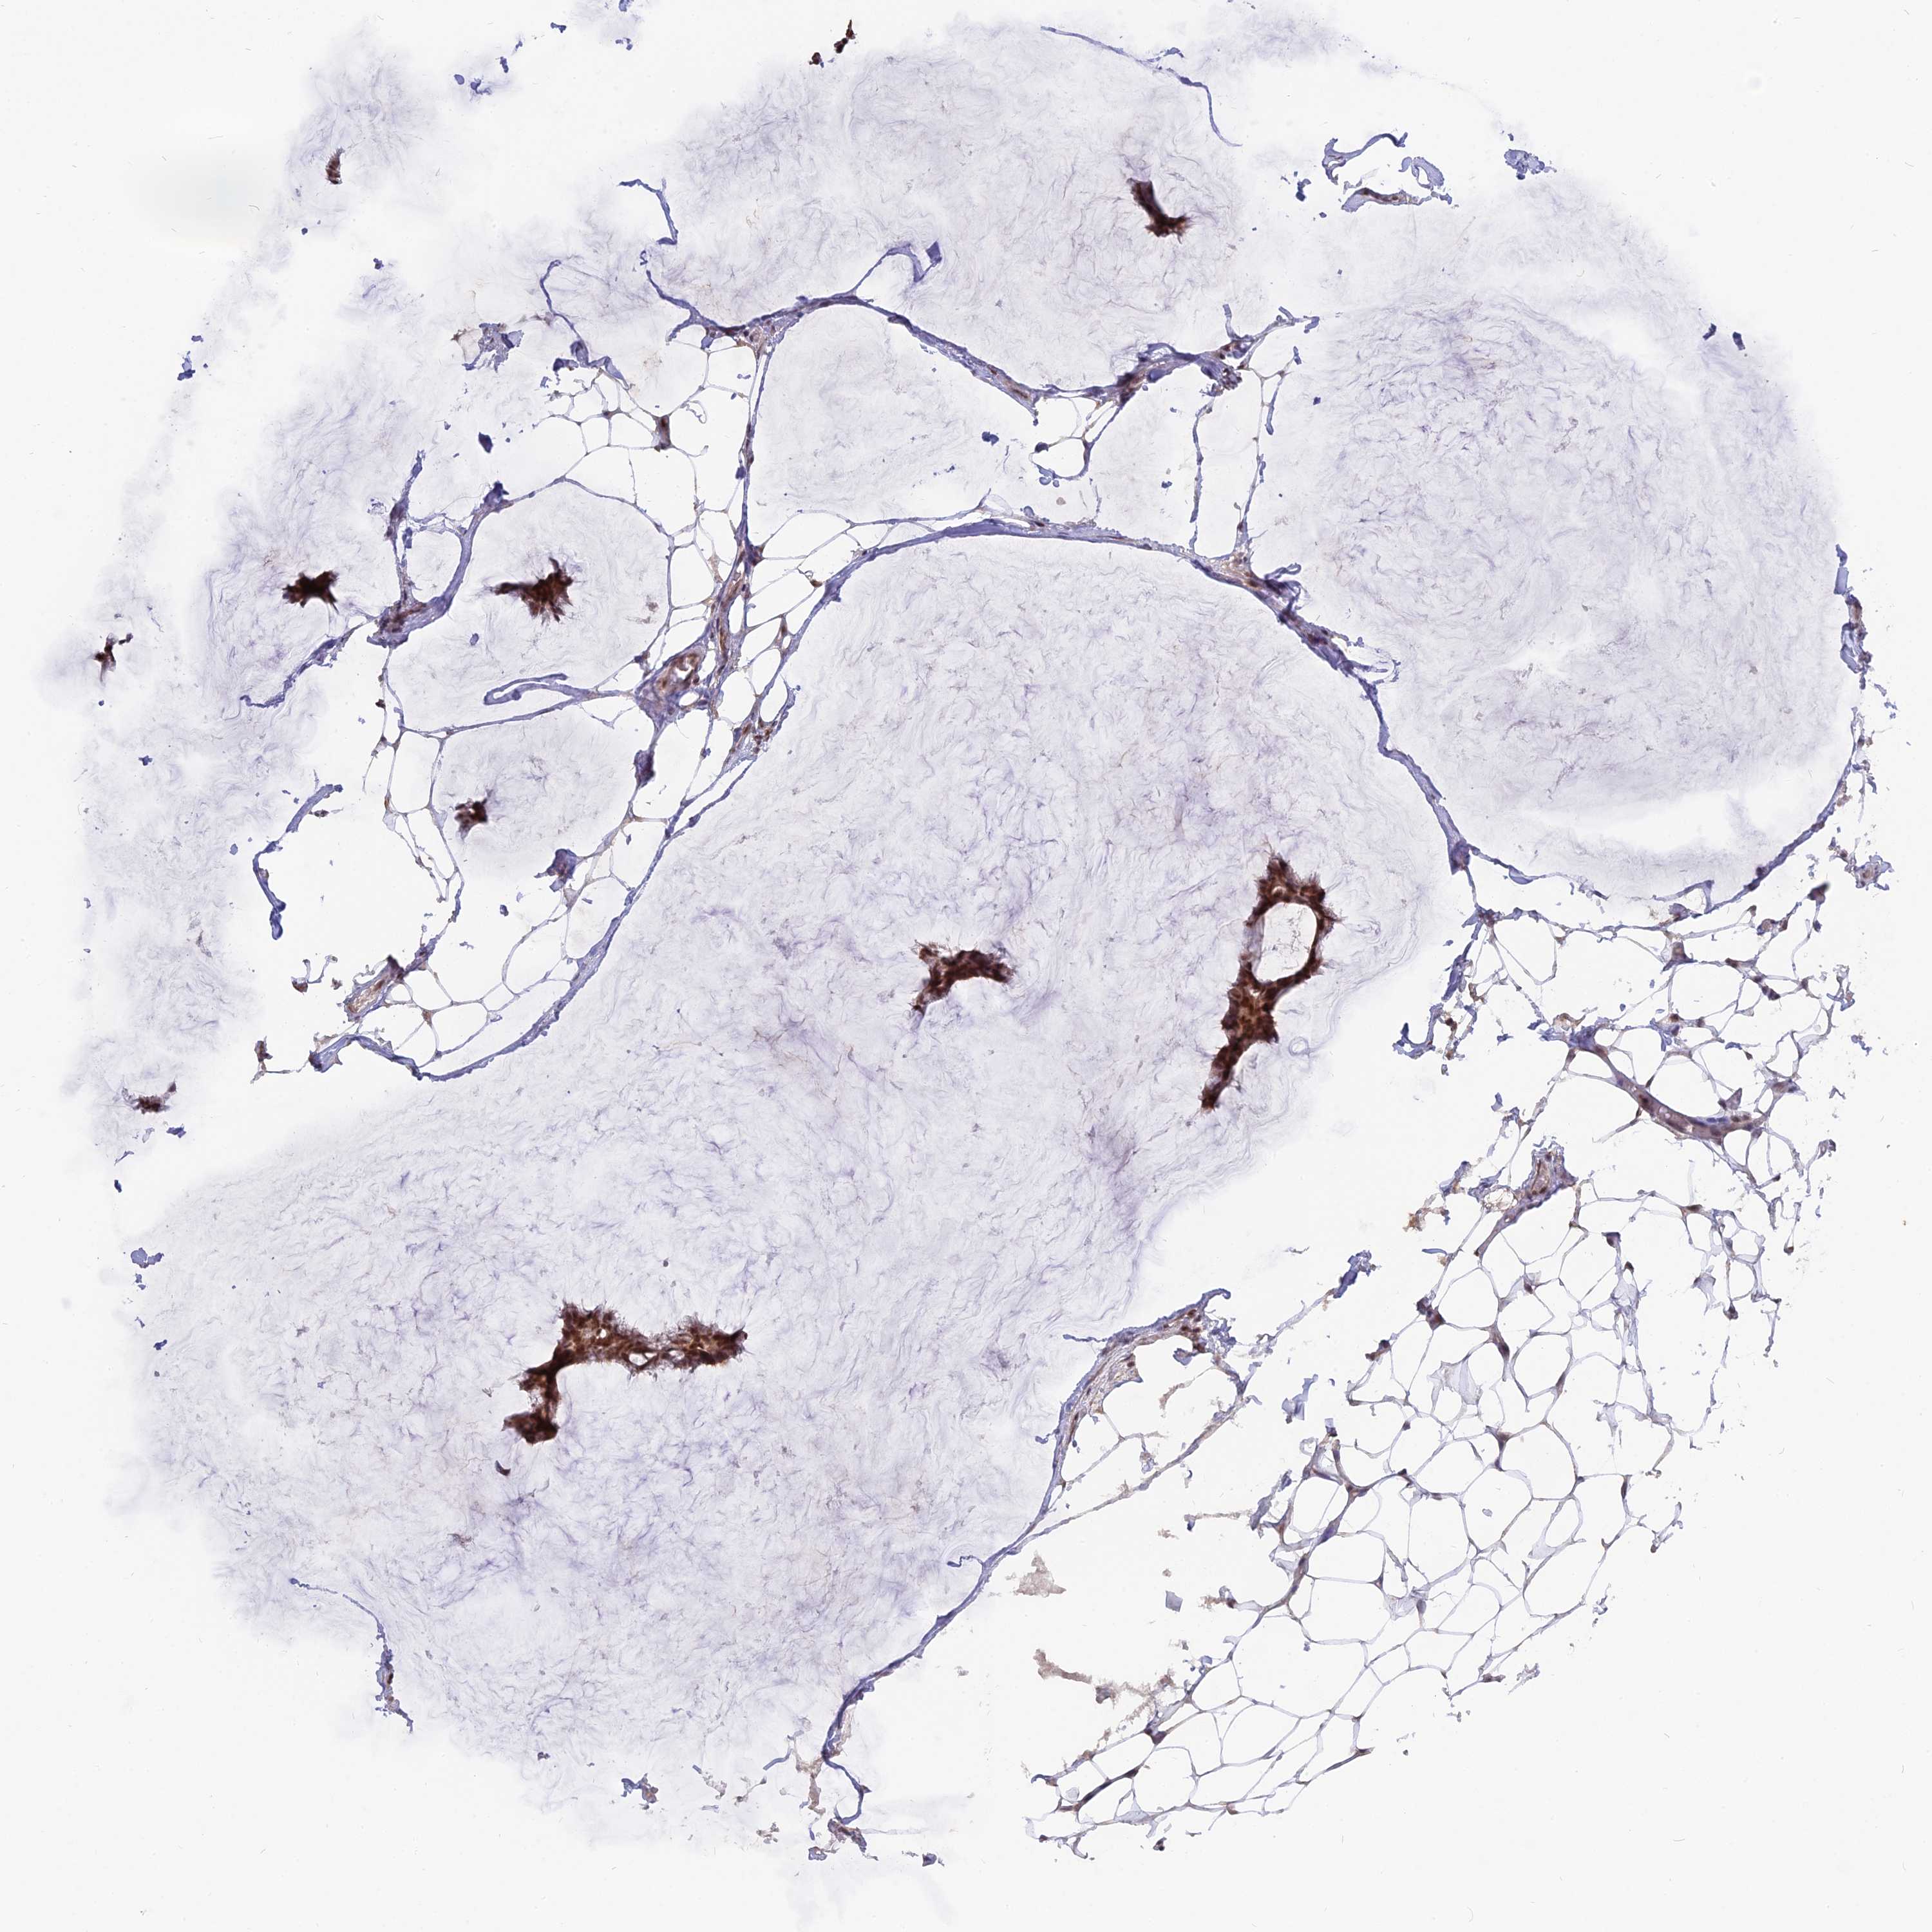

CANCER BREAST CANCER Show tissue menu

BRCA TCGA BRCA VALIDATION PROTEIN EXPRESSION